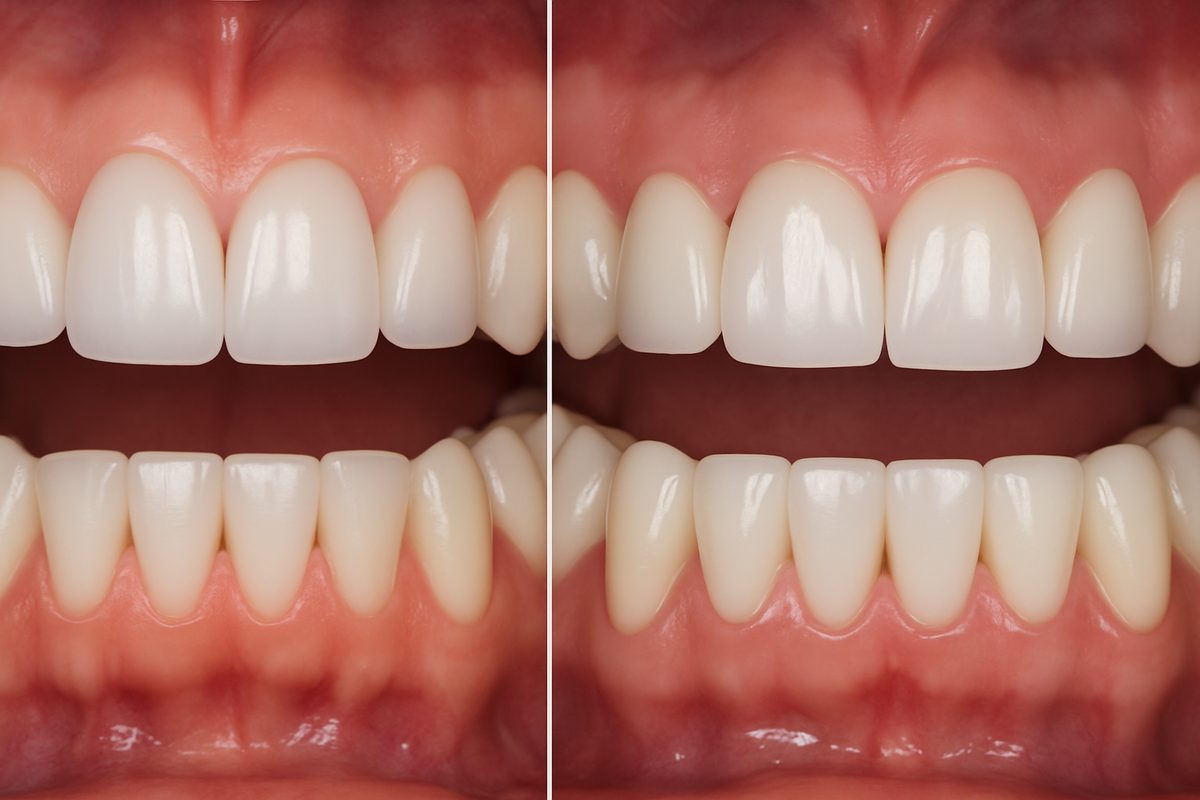

Osseointegration & Final Restoration

Over weeks to months the bone fuses to the implant in a process called osseointegration. Once stable, the abutment is attached and a custom crown, bridge, or denture is made and placed. Final restorations restore chewing, speech, and appearance.